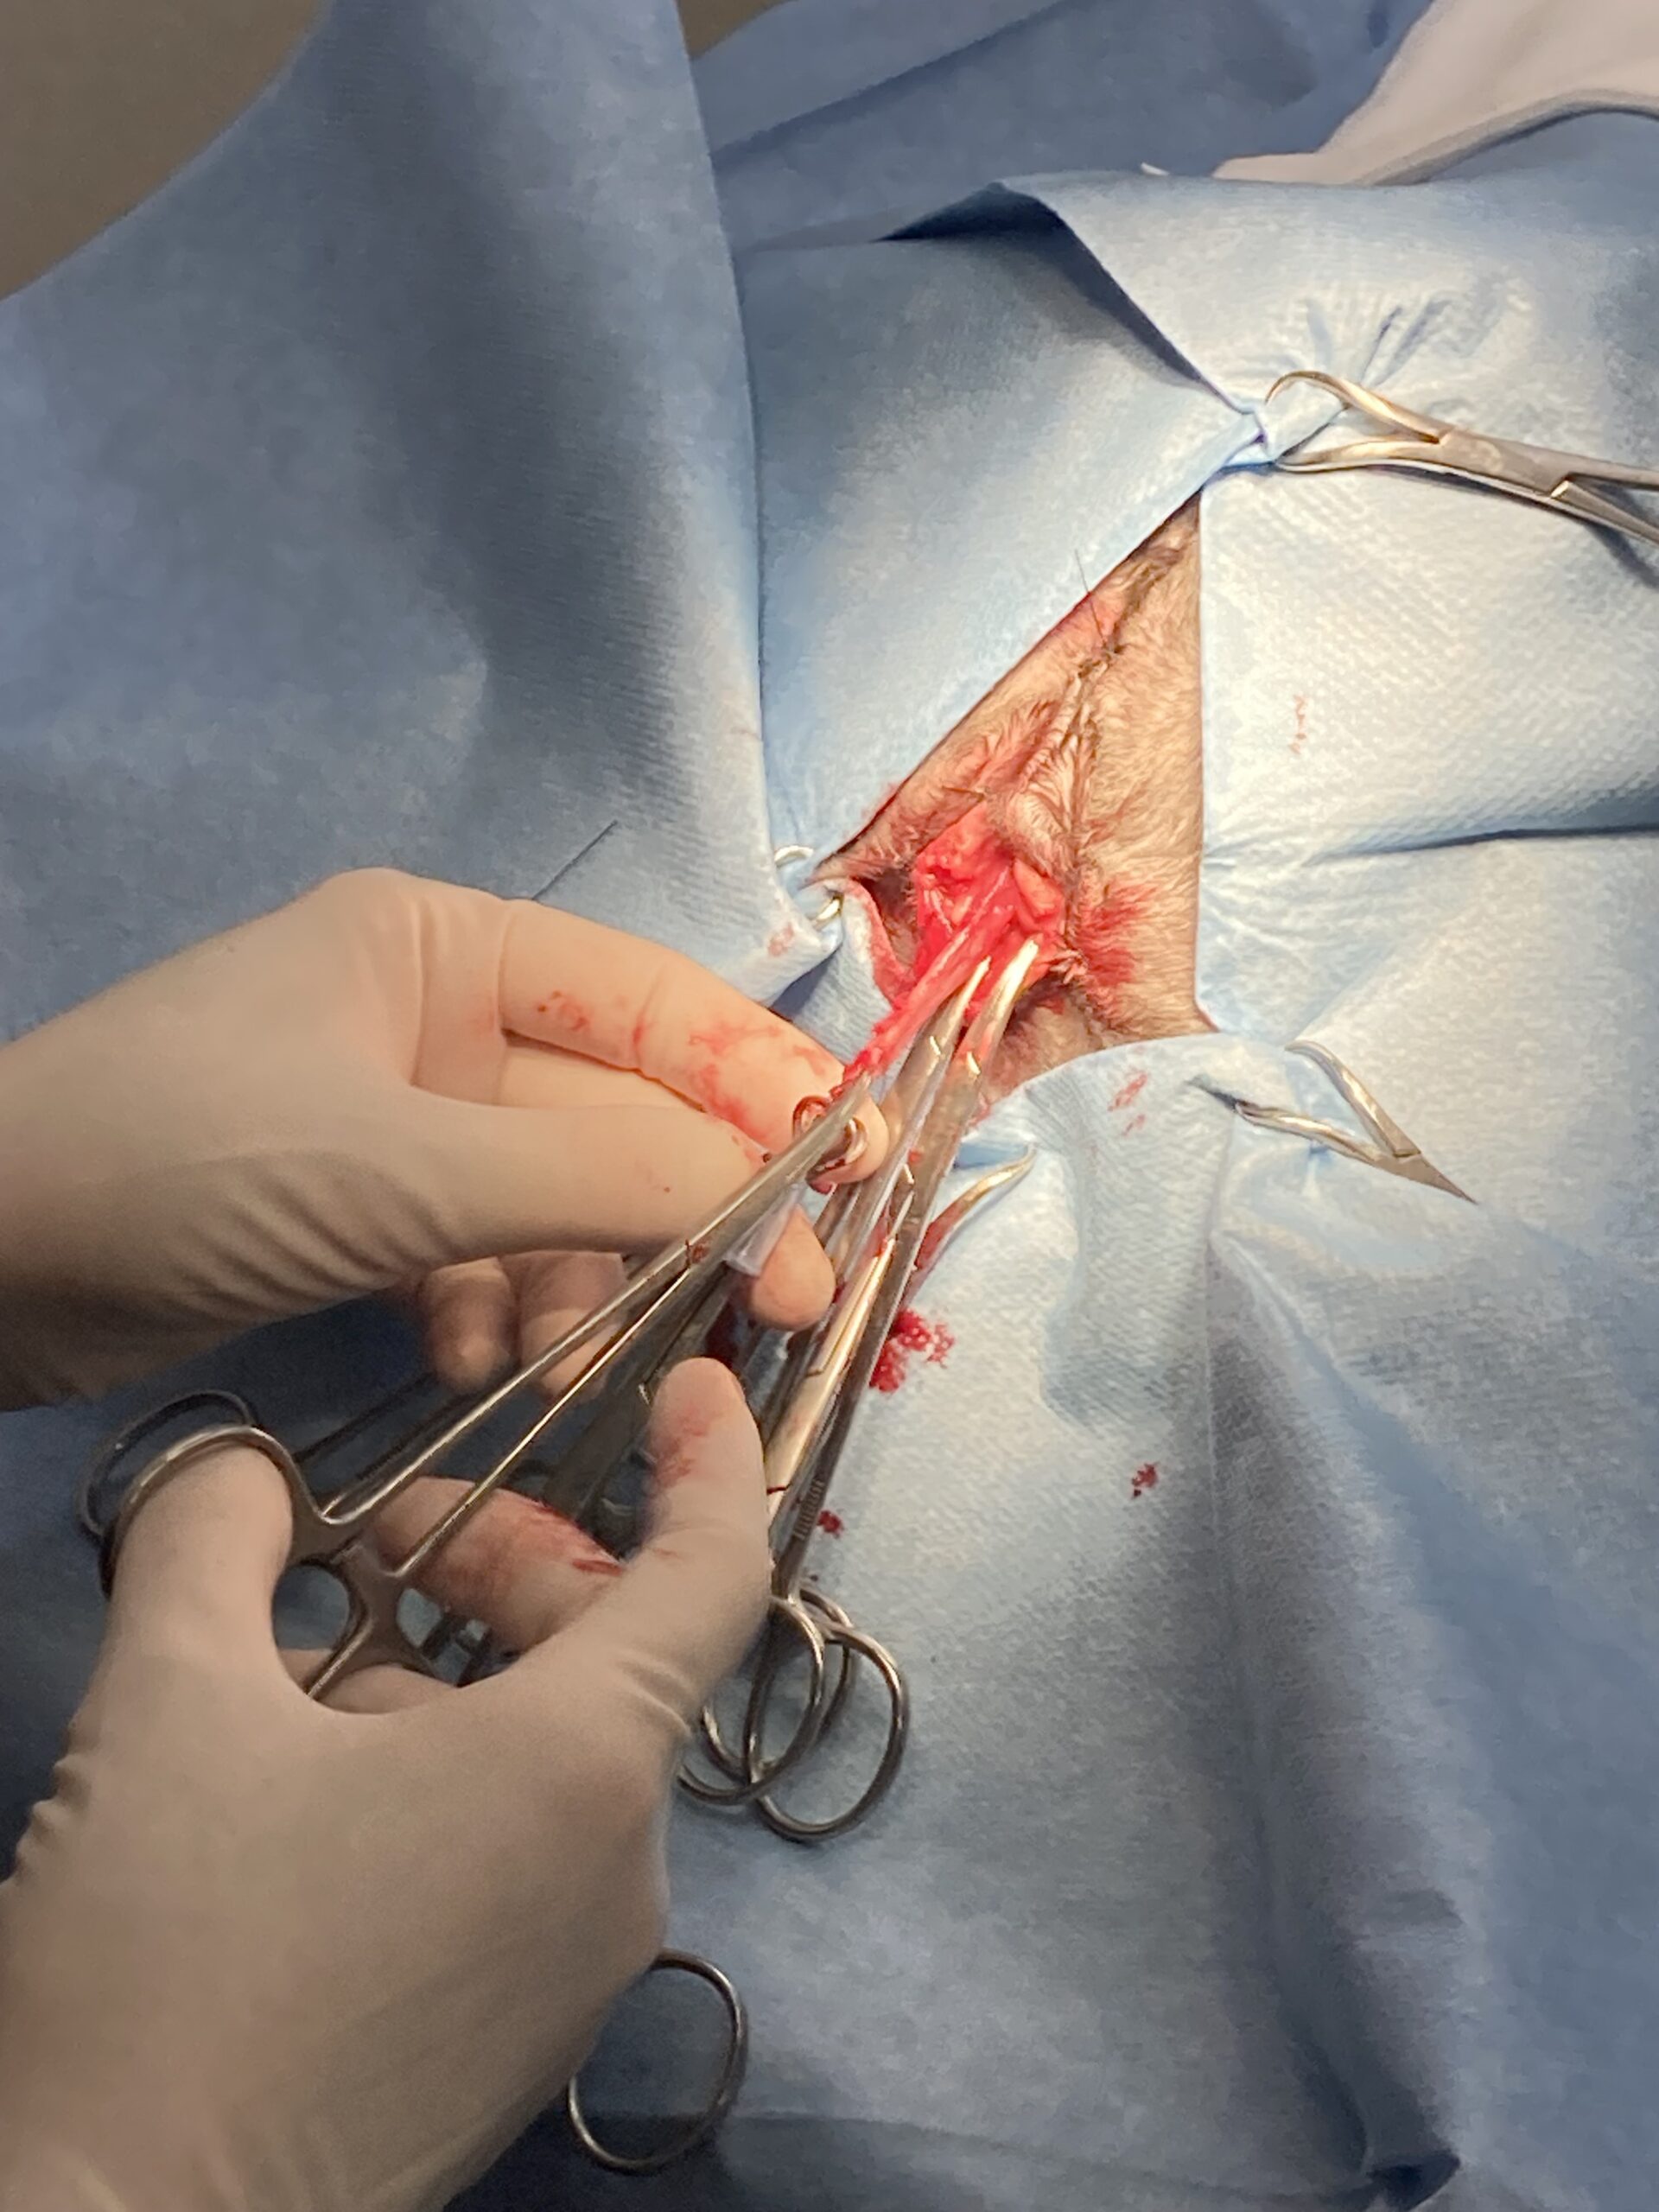

術前の超音波検査において、膀胱は極限まで拡張し、膀胱壁は今にも破裂しそうなほど薄くなっている危険な状態でした。直ちに緊急処置として膀胱穿刺を行い、ほぼ血液成分のみの尿を80ml抜去しました。この穿刺自体、膀胱破裂を招きかねない極めて緊迫した局面でしたが、これにより一時的な減圧に成功しました。しかし、尿道先端部での物理的な閉塞によりカテーテルの通過は不可能であり、内科的解除が困難であることから、直ちに外科的介入によって尿路を確保する適応と判断しました。

本症例は、重度の尿毒症と水腎症(尿管拡張)を併発しており、麻酔リスクは極めて高い状態でした。術中の致命的な血圧低下を防ぐため、静脈点滴に加えて術中ドパミンを使用し、循環動態を厳密に維持しました。

さらに、当院では局所浸潤麻酔を徹底して併用しています。全身の機能が低下している患者さんに対し、痛みの伝達経路を局所で物理的に遮断することで、全身麻酔薬の必要量を下げ、安全域を論理的に広げています。